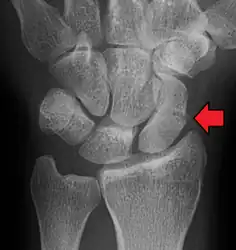

Scaphoid fractures occur in three locations: (A) Distal tubercle, (B) waist, and (C) proximal pole.

Fractures of scaphoid can occur either with direct axial compression or with hyperextension of the wrist, such as a fall on the palm on an outstretched hand (FOOSH). 10%-20% of fractures are at the proximal pole, 60%-80% are at the waist (middle), and the remainder occur at the distal pole.[4][7][5]